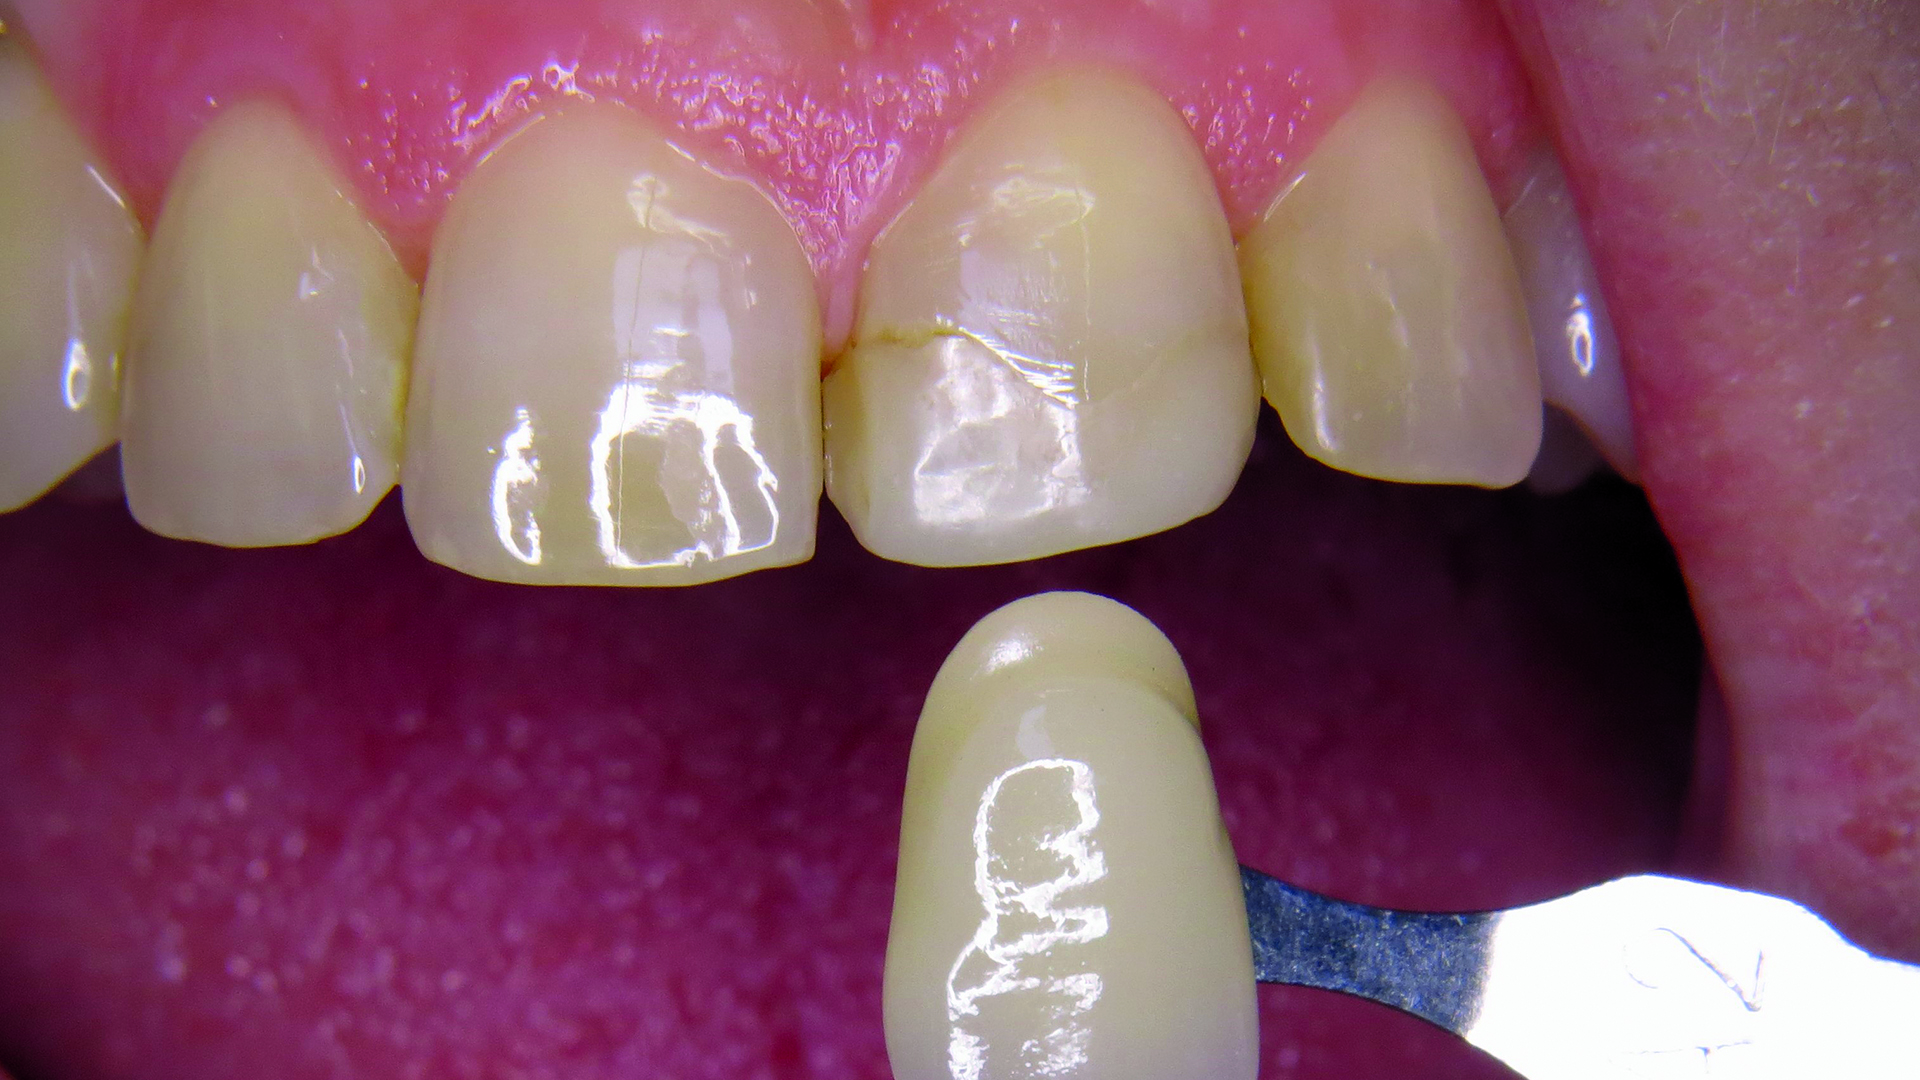

Z gamy odcieni klastrowych wybrano odcień A2 (ryc. 2). Następnie pobrano wycisk masą V-Posil Putty Fast (VOCO GmbH, Niemcy) w celu stworzenia modelu gipsowego. Z materiału Registrado Clear (VOCO GmbH, Niemcy) wykonano indywidualny klucz silikonowy do nadbudowy powierzchni podniebiennej (ryc. 3).

Ryc. 2. Łatwy dobór odcienia.